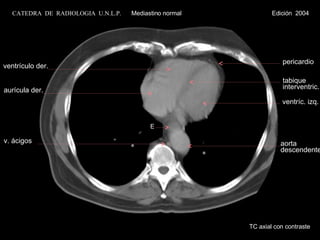

TC axial concontraste ventrículo der. aurícula izq. v. ácigos aurícula der. aorta descendente CATEDRA DE RADIOLOGIA U.N.L.P. Mediastino normal Edición 2004 ventrículo izq. tabique interventric. pericardio

TC axial con contraste ventrículo der. aurícula izq. v. ácigos aurícula der. aorta descendente CATEDRA  DE  RADIOLOGIA  U.N.L.P.   Mediastino normal  Edición  2004 ventrículo izq. tabique interventric. pericardio